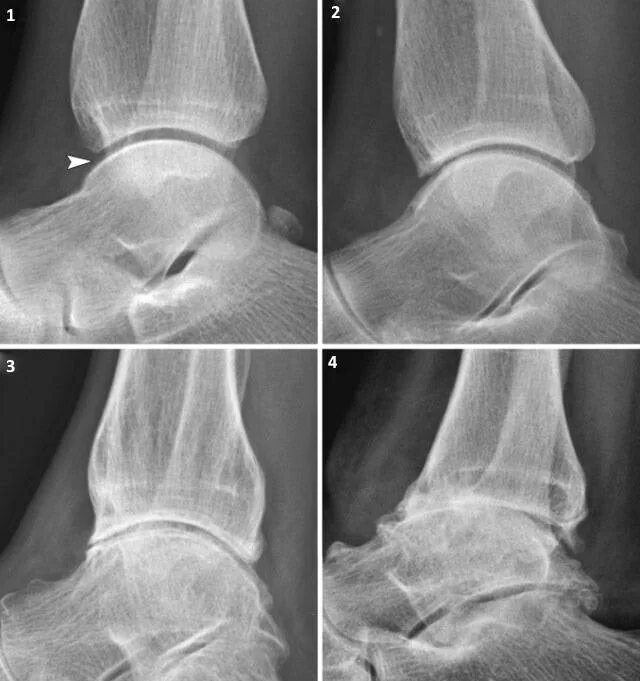

Артроз голеностопного сустава код